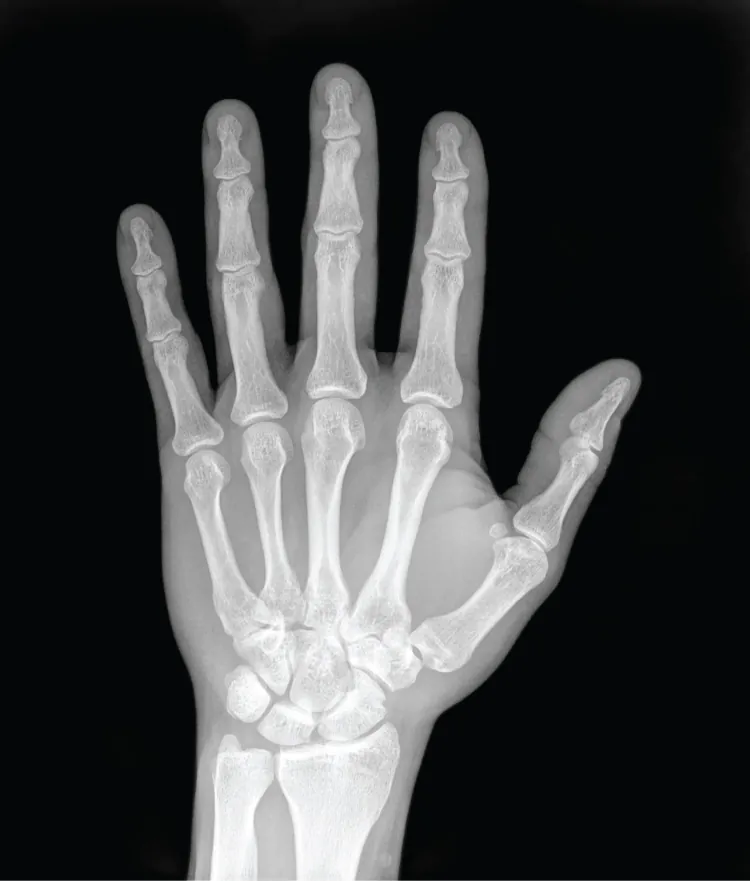

The X-ray is a form of high energy electromagnetic radiation with a short wavelength capable of penetrating solids and ionizing gases. As they are used in medicine, X-rays are emitted from an X-ray machine and directed toward a specially treated metallic plate placed behind the patient’s body. The beam of radiation results in darkening of the X-ray plate. X-rays are slightly impeded by soft tissues, which show up as gray on the X-ray plate, whereas hard tissues, such as bone, largely block the rays, producing a light-toned “shadow.” Thus, X-rays are best used to visualize hard body structures such as teeth and bones (Figure 1.18). Like many forms of high energy radiation, however, X-rays are capable of damaging cells and initiating changes that can lead to cancer. This danger of excessive exposure to X-rays was not fully appreciated for many years after their widespread use.

This photo shows an X ray image of the palmar surface of the left hand. The bones appear bright white against a gray outline of the skin of the hand. The four segments of the finger bones are clearly visible, as well as the collection of round bones that compose the wrist and connect the hand to the two bones of the forearm.

Figure 1.18 X-Ray of a Hand High energy electromagnetic radiation allows the internal structures of the body, such as bones, to be seen in X-rays like these. (credit: Trace Meek/flickr)